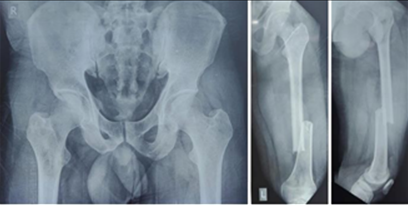

None of the patients experienced post-operative knee or hip stiffness after undergoing combination fixation with an intramedullary nail and derotation plate. X-rays of the patient with follow-ups at 3 months and 6 months(Fig. 1, 2, 3, 4).

Figure 1: Showing pre-operative X-rays.